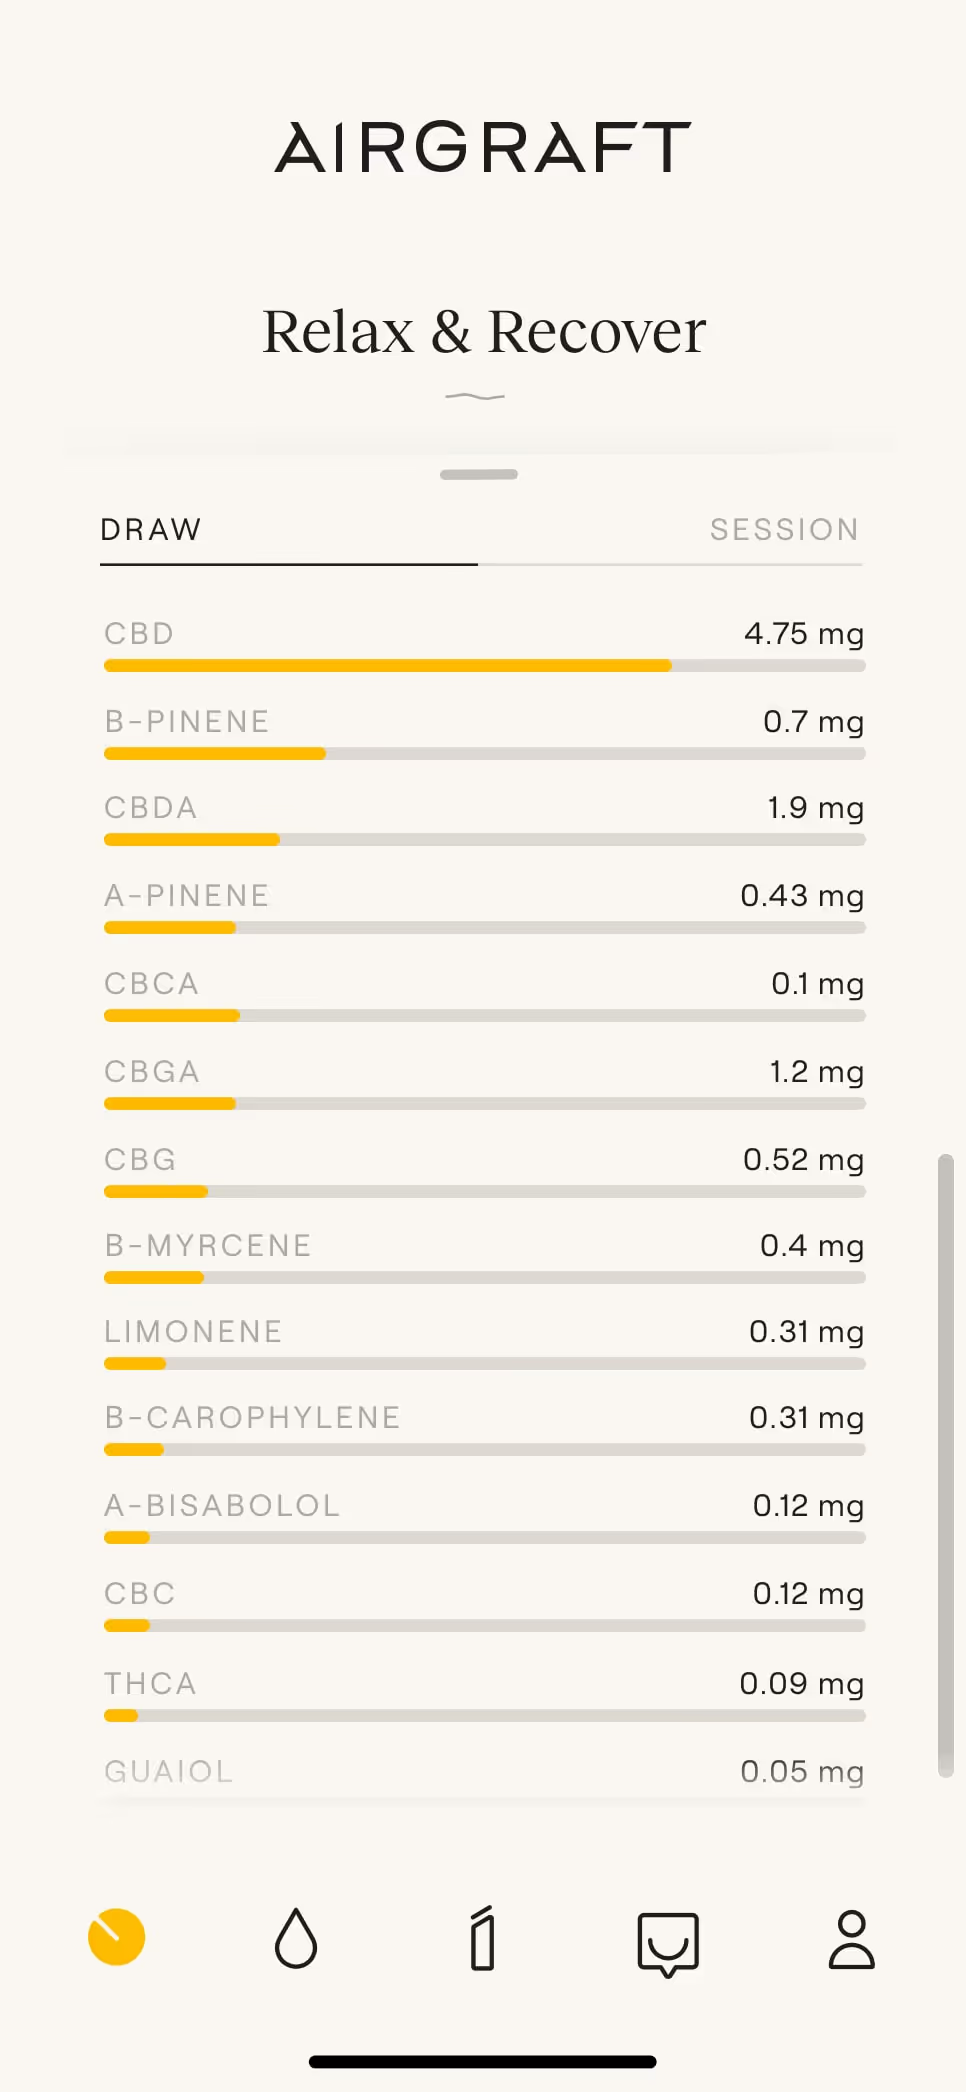

Airgraft

Selected Projects

Project images

Type

Services

Credits